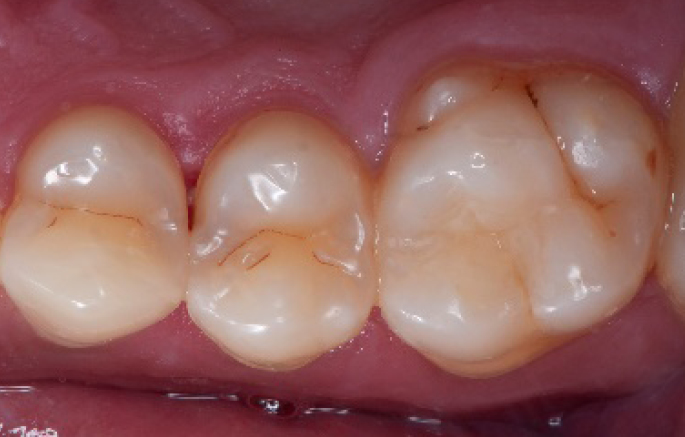

Initial situation of the patient

The patient came for a routine control appointment. She didn‘t report any symptoms but some bleeding during brushing.

Before

Initial situation: an old class I composite restoration on 1.6. New caries on the mesial wall. Presence of plaque and inflammation.